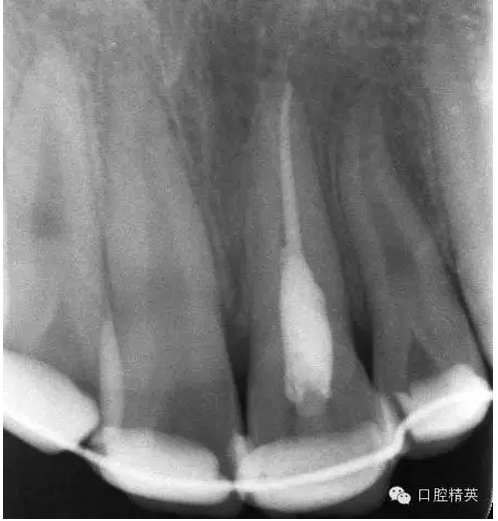

圖18.復(fù)位臨時(shí)固定后的x線根尖片?;颊哐栏c牙槽窩吻合。

圖19.經(jīng)過(guò)x線檢查,21復(fù)位和牙槽窩吻合,行13到23粘結(jié)部位的牙面全酸蝕。

圖23.樹(shù)脂+牙弓夾板固定完成后的x線片影像